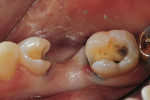

In vitro studies have demonstrated that the use of unidirectional glass-fiber reinforcement in the connector areas of FPDs contributes to significant composite reinforcement.29,36-38,66-68 Similar findings have been reported with a leno-weave UHMWPE and triaxial weave UHMWPE fiber.20,33,36 Fiber-reinforcing materials used by a dental laboratory are either resin pre-impregnated glass fibers, pre-polymerized composite resin surrounding glass fibers, biaxial braid UHMWPE, leno-weave UHMWPE, or a triaxial weave UHMWPE (Table 3). Typically, the preparation designs for the abutment teeth are inlay or onlay preparations (Figure 6A, Figure 6B, Figure 6C, Figure 6D). They are highly successful and can provide the patient with clinical service for more than 5 to 10 years.69 These restorations must be cemented using an adhesive resin technique with resin cements. Both etch-and-rinse adhesives with a self-cure or dual-cure composite resin cement or with a self-adhesive resin cement are indicated for cementing these restorations (Figure 7).36-38,70 Also, fiber-reinforcing materials are being used by dental laboratories in the fabrication of provisional restorations to reinforce and strengthen acrylic and composite-resin provisional materials.15,40,71